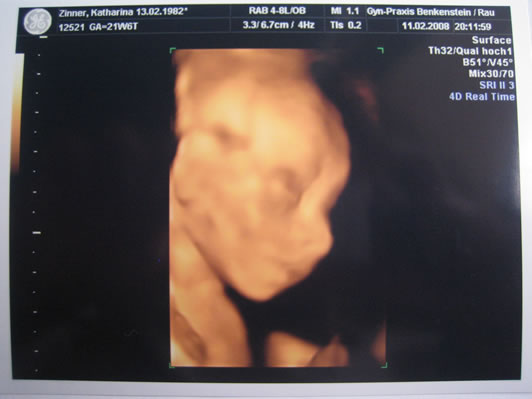

Vorgestern waren Mama und Papa mit mir zur Feindiagnostik. Da haben sie mich dann zum ersten Mal 4-dimensional gesehen.

Die Ärztin meinte, ich sei ein hübsches Baby - danke! Es ist alles heile an mir und ich entwickle mich prächtig.

Ich bin mittlerweile stolze 23 cm groß und wiege 350 g. Mama bin ich auch noch nicht zu schwer, sie hat noch keine Probleme mit dem Bauch, den ich forme... Mamis Bauch hat zur Zeit einen Umfang von 96 cm und sie wiegt stolze 4 kg mehr als vor der Schwangerschaft.